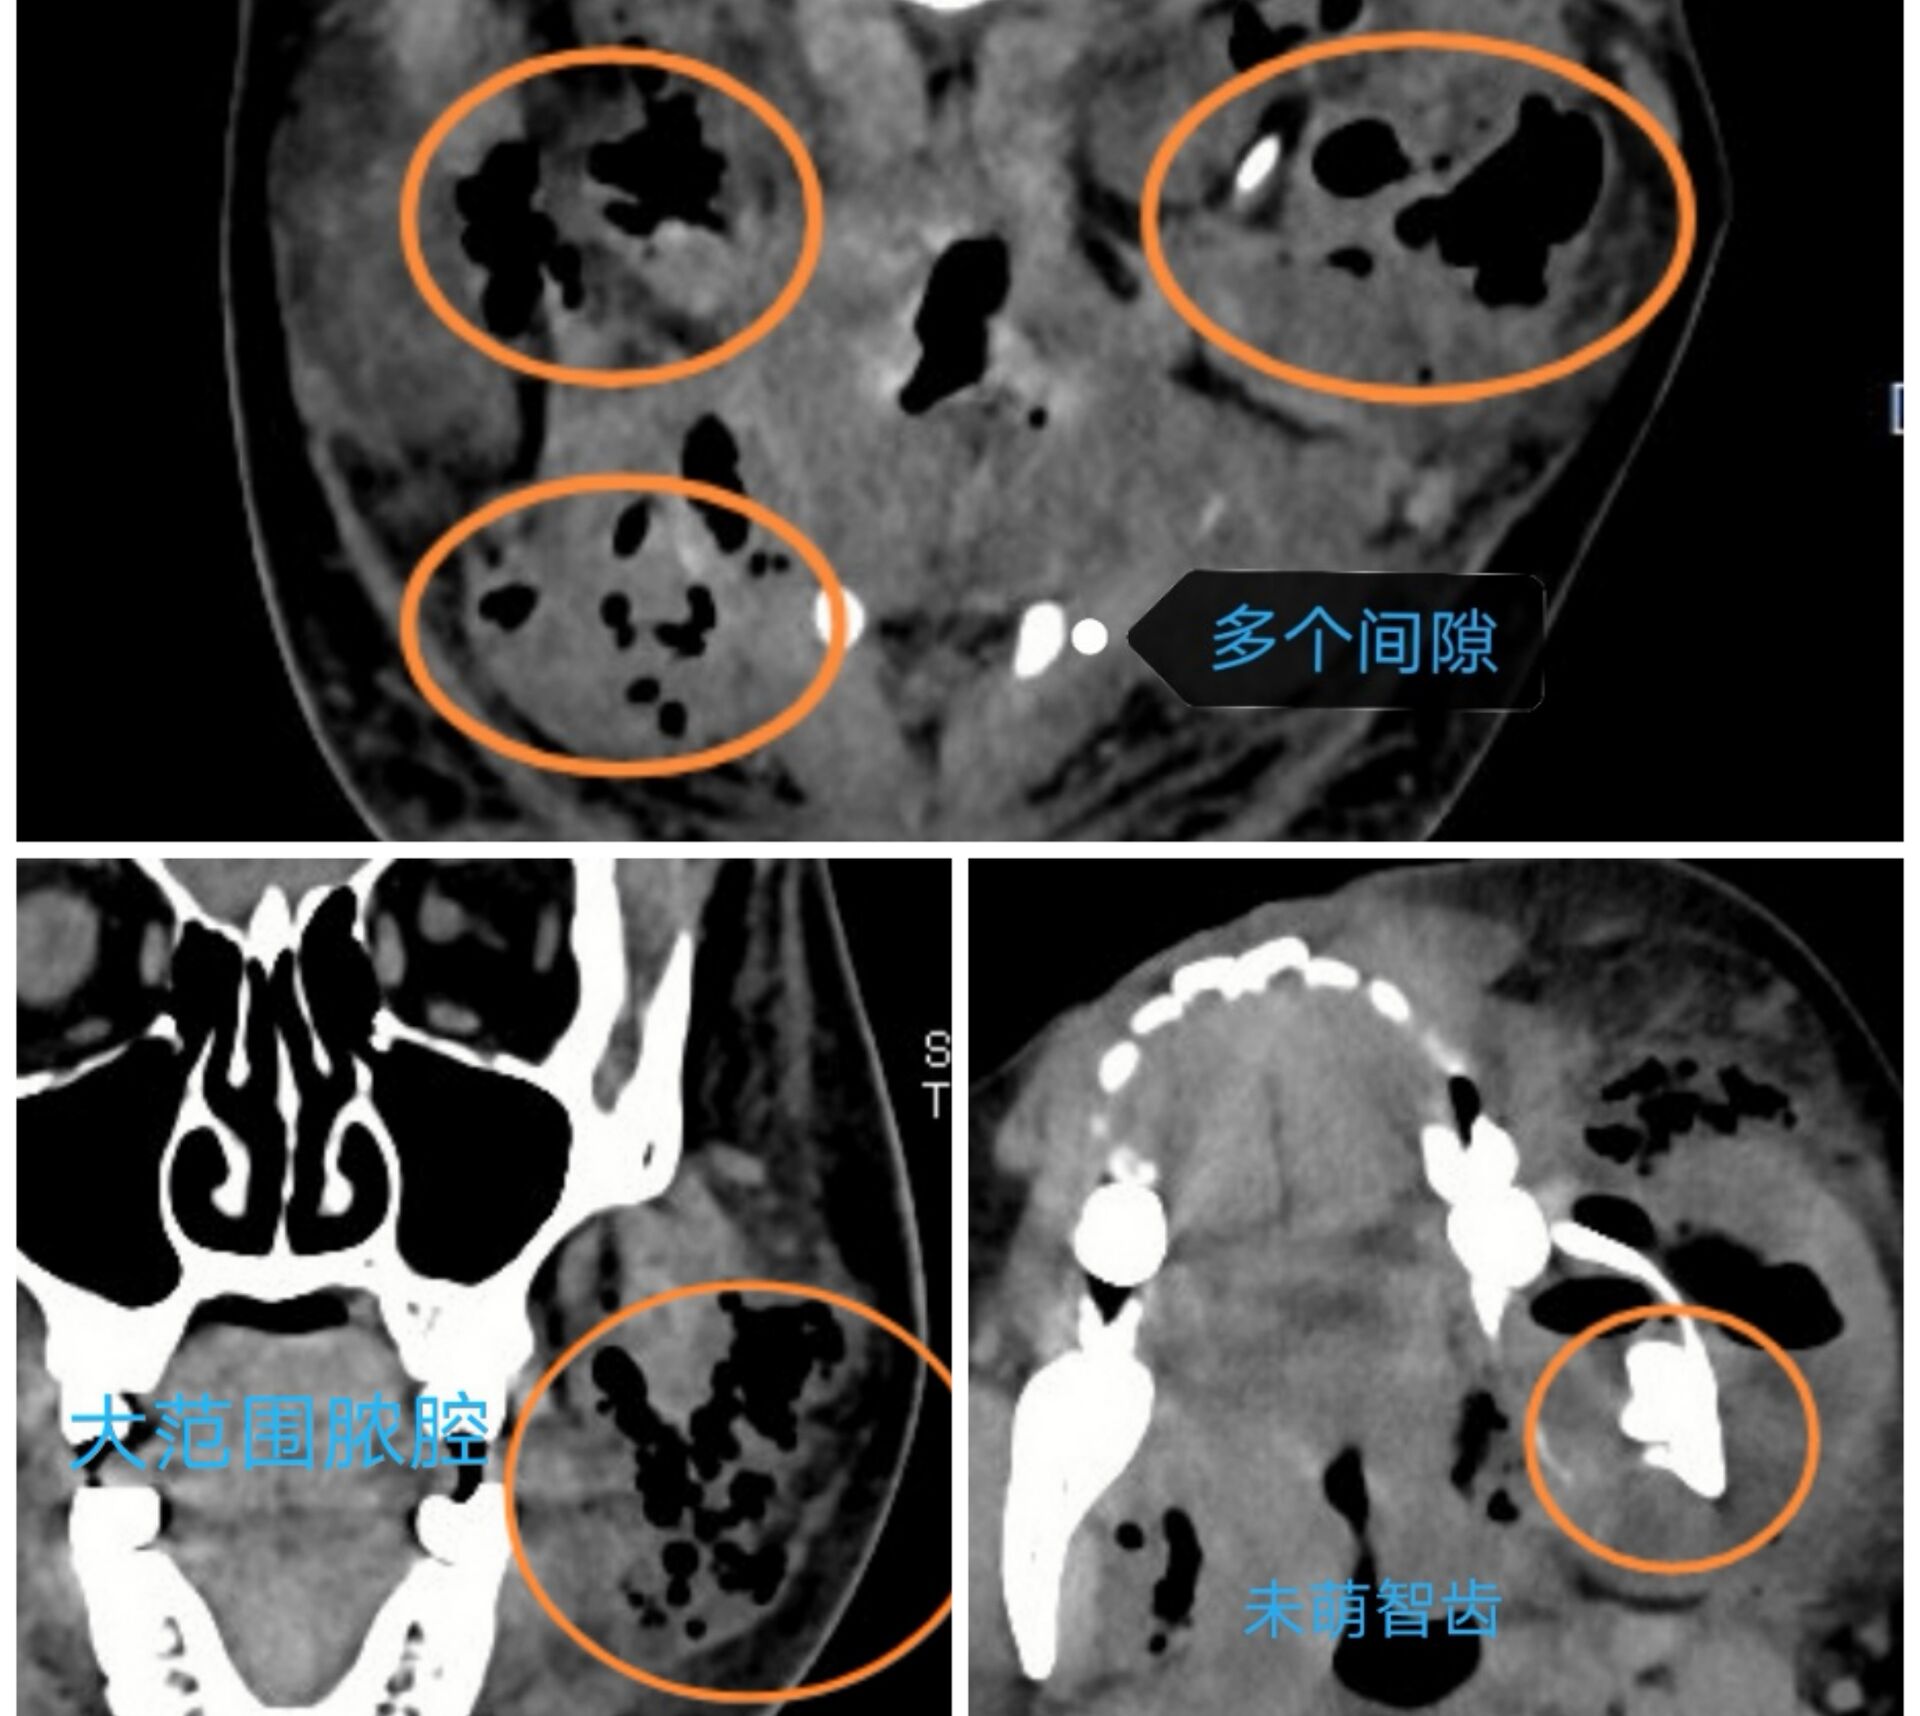

智齿容易引起感染,损害健康,甚至危及生命。如,一,冠周牙龈软组织引起的发炎。智齿萌出不全,部分牙龈覆盖,容易积存食物导致局部牙龈肿痛、化脓。这种情况尚属轻症,通过局部处理,口服抗生素即可恢复。冠周炎若治疗不及时,也有小部分会发展成邻间隙感染,此时症状严重,伴有发热、乏力等全身症状,只有通过手术才能治愈;二,龋坏智齿。细菌通过根管内牙髓组织,到达根尖区颌骨,引起感染。智齿牙根一般都比较深,尤其是牙根尖,感染继续扩散的话,就会造成颌面多间隙的感染,损害健康,危及生命。

病历一